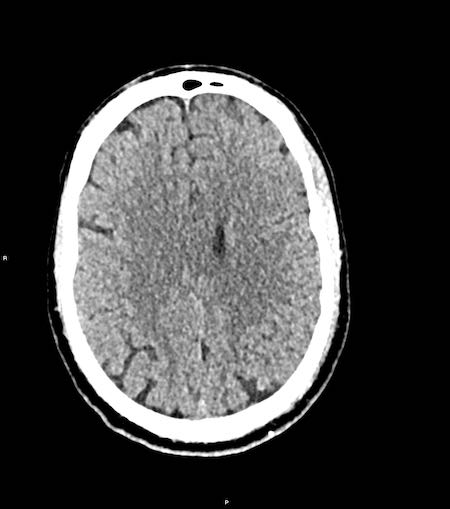

Các hình ảnh cho thấy tụ máu dưới màng cứng.

Lưu ý rằng khối tụ máu có cả vùng tăng tỷ trọng và đồng tỷ trọng.

Hình ảnh này có thể gặp trong chảy máu siêu cấp tính, nhưng cũng có thể gặp trong trường hợp chảy máu tái phát.

Có sự dịch chuyển các cấu trúc đường giữa kèm tắc nghẽn lưu thông dịch não tủy, dẫn đến giãn sừng thái dương của não thất bên phải (mũi tên).